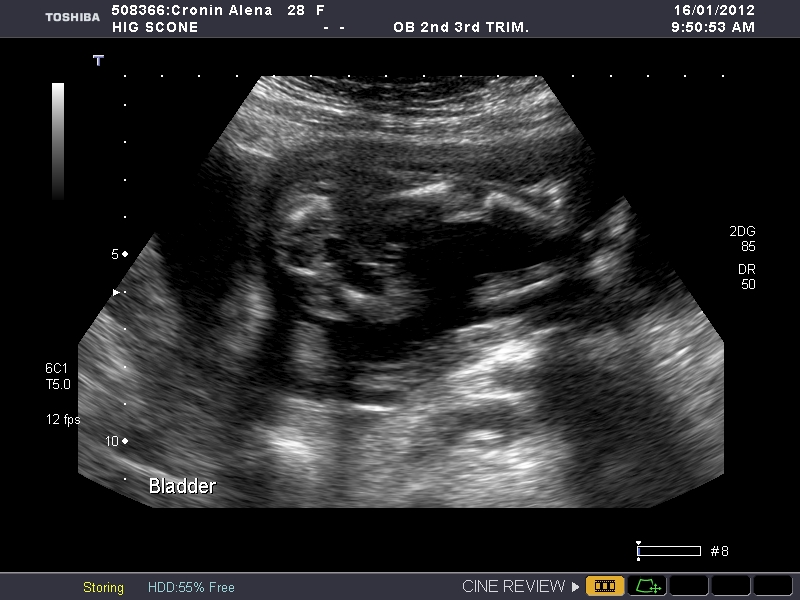

So bub was very uncooperative but the ultrasound tech tells me she can't see anything so she thinks its a :DD: :cheer::cheer::cheer: I am so excited. So do you girls agree?

I see 3 white lines = girl. (Which, in my opinion, is a LOT better than "no boy parts.") Congrats!

If this is a potty shot its a girl :)